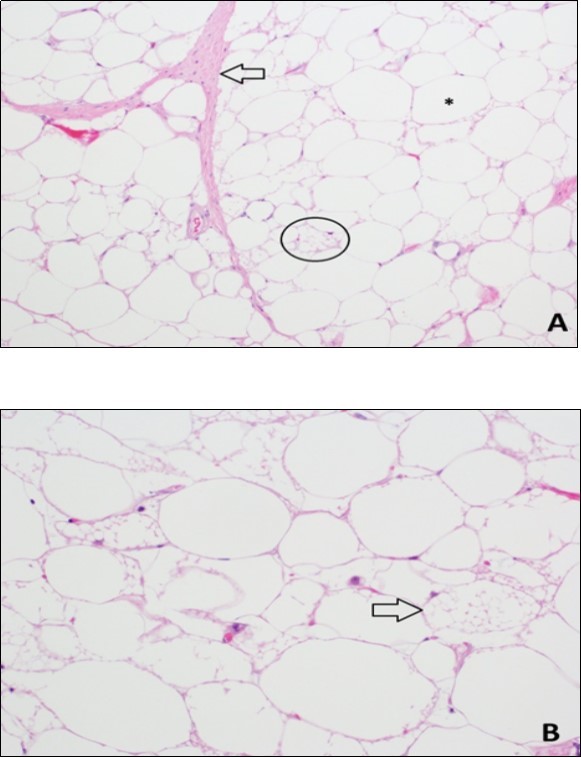

A 13 year old male presented to his local physician with a painless, slowly enlarging palpable mass of the proximal right thigh. Contrast-enhanced MRI was performed which raised concern for soft tissue sarcoma. We were consulted for a second opinion interpretation of the imaging study and recommendations for management. Outside multi-planar and multi-weighted MRI demonstrated a large lipomatous anterior compartmental thigh mass (Figure 1A-D). The mass was predominantly fatty with the majority of the tumor following the signal intensity of subcutaneous fat on both T1-weighted and fat-suppressed images. Internal enhancing nodularity (Figure 1B) and slightly thickened septations (Figure 1C) argued against simple lipoma and did initially raise concern for liposarcoma; however, liposarcomas are extremely rare in children. MRI findings of a slightly complex mostly fat containing mass with mild nodularity and thin internal septations are often seen in atypical lipomatous tumors. While greater than most reported lipoblastomas, patient age was felt to be more suggestive of lipoblastoma than ALT. Imaging features were not consistent with a simple purely fatty lesion such as lipoma and lack of any dominant internal non-adipocytic soft tissue elements argued against dedifferentiated liposarcoma. Under the care of an outside orthopedic surgeon, the patient underwent uncomplicated resection of the mass with negative margins and recovered well following surgery; gross tumor size and description of capsule at outside surgery are not available. Histopathology confirmed a lipomatous neoplasm with mature appearing white adipocytes lacking atypia or nuclear pleomorphism and several internal fibrous septae (Figure 2). Additionally, numerous interspersed multivacuolated brown fat cells with granular eosinophilic cytoplasm were identified yielding a final unexpected pathologic diagnosis of hibernoma.

Hibernoma is a benign lipomatous neoplasm most commonly occurring in early to middle aged adults and most often involving the proximal extremities (thigh, arm), neck, and trunk 8. Complete surgical removal is considered curative with no known cases of distant metastatic disease and only limited reports of local tumor recurrence attributed to incomplete resection 8. Histologically, they contain white and brown fat cells, multivacuolated fat cells with eosinophilic cytoplasm and small central nuclei lacking atypia (Figure 2). Nests or regions of densely packed lipoblasts with less intracytoplasmic lipid correlate with internal nodularity seen at MRI, while band-like sheets of fibroblasts form the internal septae. Four histologic variants are recognized: typical, spindle cell, lipoma-like, and myxoid hibernomas 8. These histologic subtypes may demonstrate suggestive imaging features such as a predominance of simple fat (i.e. lipoma-like), a greater degree of internal fat stranding (spindle cell), or areas of myxomatous signal (myxoid), however findings are inconsistently seen at imaging and lack specificity or sensitivity to reliably subtype hibernomas at MRI. As seen herein, simply differentiating hibernoma from other benign lipomatous neoplasms can prove difficult at preoperative imaging. A study performed to assess MRI readers’ ability to distinguish hibernomas from lipomas and atypical lipomatous tumors noted that diffusely decreased T1-weighted signal intensity falling somewhere between fat and skeletal muscle and visualization of dilated internal blood vessels within the mass were the most helpful features in suggesting hibernoma 9. Neither of these findings was appreciated in this case. While the proximal thigh is a common site of disease in hibernoma, the vast majority occur in adults rather than children. In the largest published series to date, 170 hibernomas from the Armed Forces Institute of Pathology were reviewed demonstrating a mean age of 38 years, only 9 of which occurred in pediatric patients 8. Conversely, lipoblastoma is exclusively a tumor of children, most presenting prior to 3 years of age with few reports in teen aged patients 10, 11. Brown fat plays an active role in thermogenesis and is known to demonstrate intense F-18 fluorodeoxyglucose (FDG) uptake on positron emission tomography (PET). Similarly, hibernomas which contain brown fat cells have been shown to demonstrate marked FDG avidity, as opposed to most other benign fatty tumors, which may help correctly identify hibernoma prior to surgery 12. Preoperative PET imaging was not performed in this case.

Figure 2.Histopathology of lipomatous mass. A. Hematoxylin and eosin stain (10X) demonstrates fibrous septae (arrow), mature white adipocytes (*), and multivacuolated brown fat cells (circle). B. Hematoxylin and eosin stain (20X) demonstrates several multivacuolated brown fat cells (arrow) with granular eosinophilic cytoplasm.